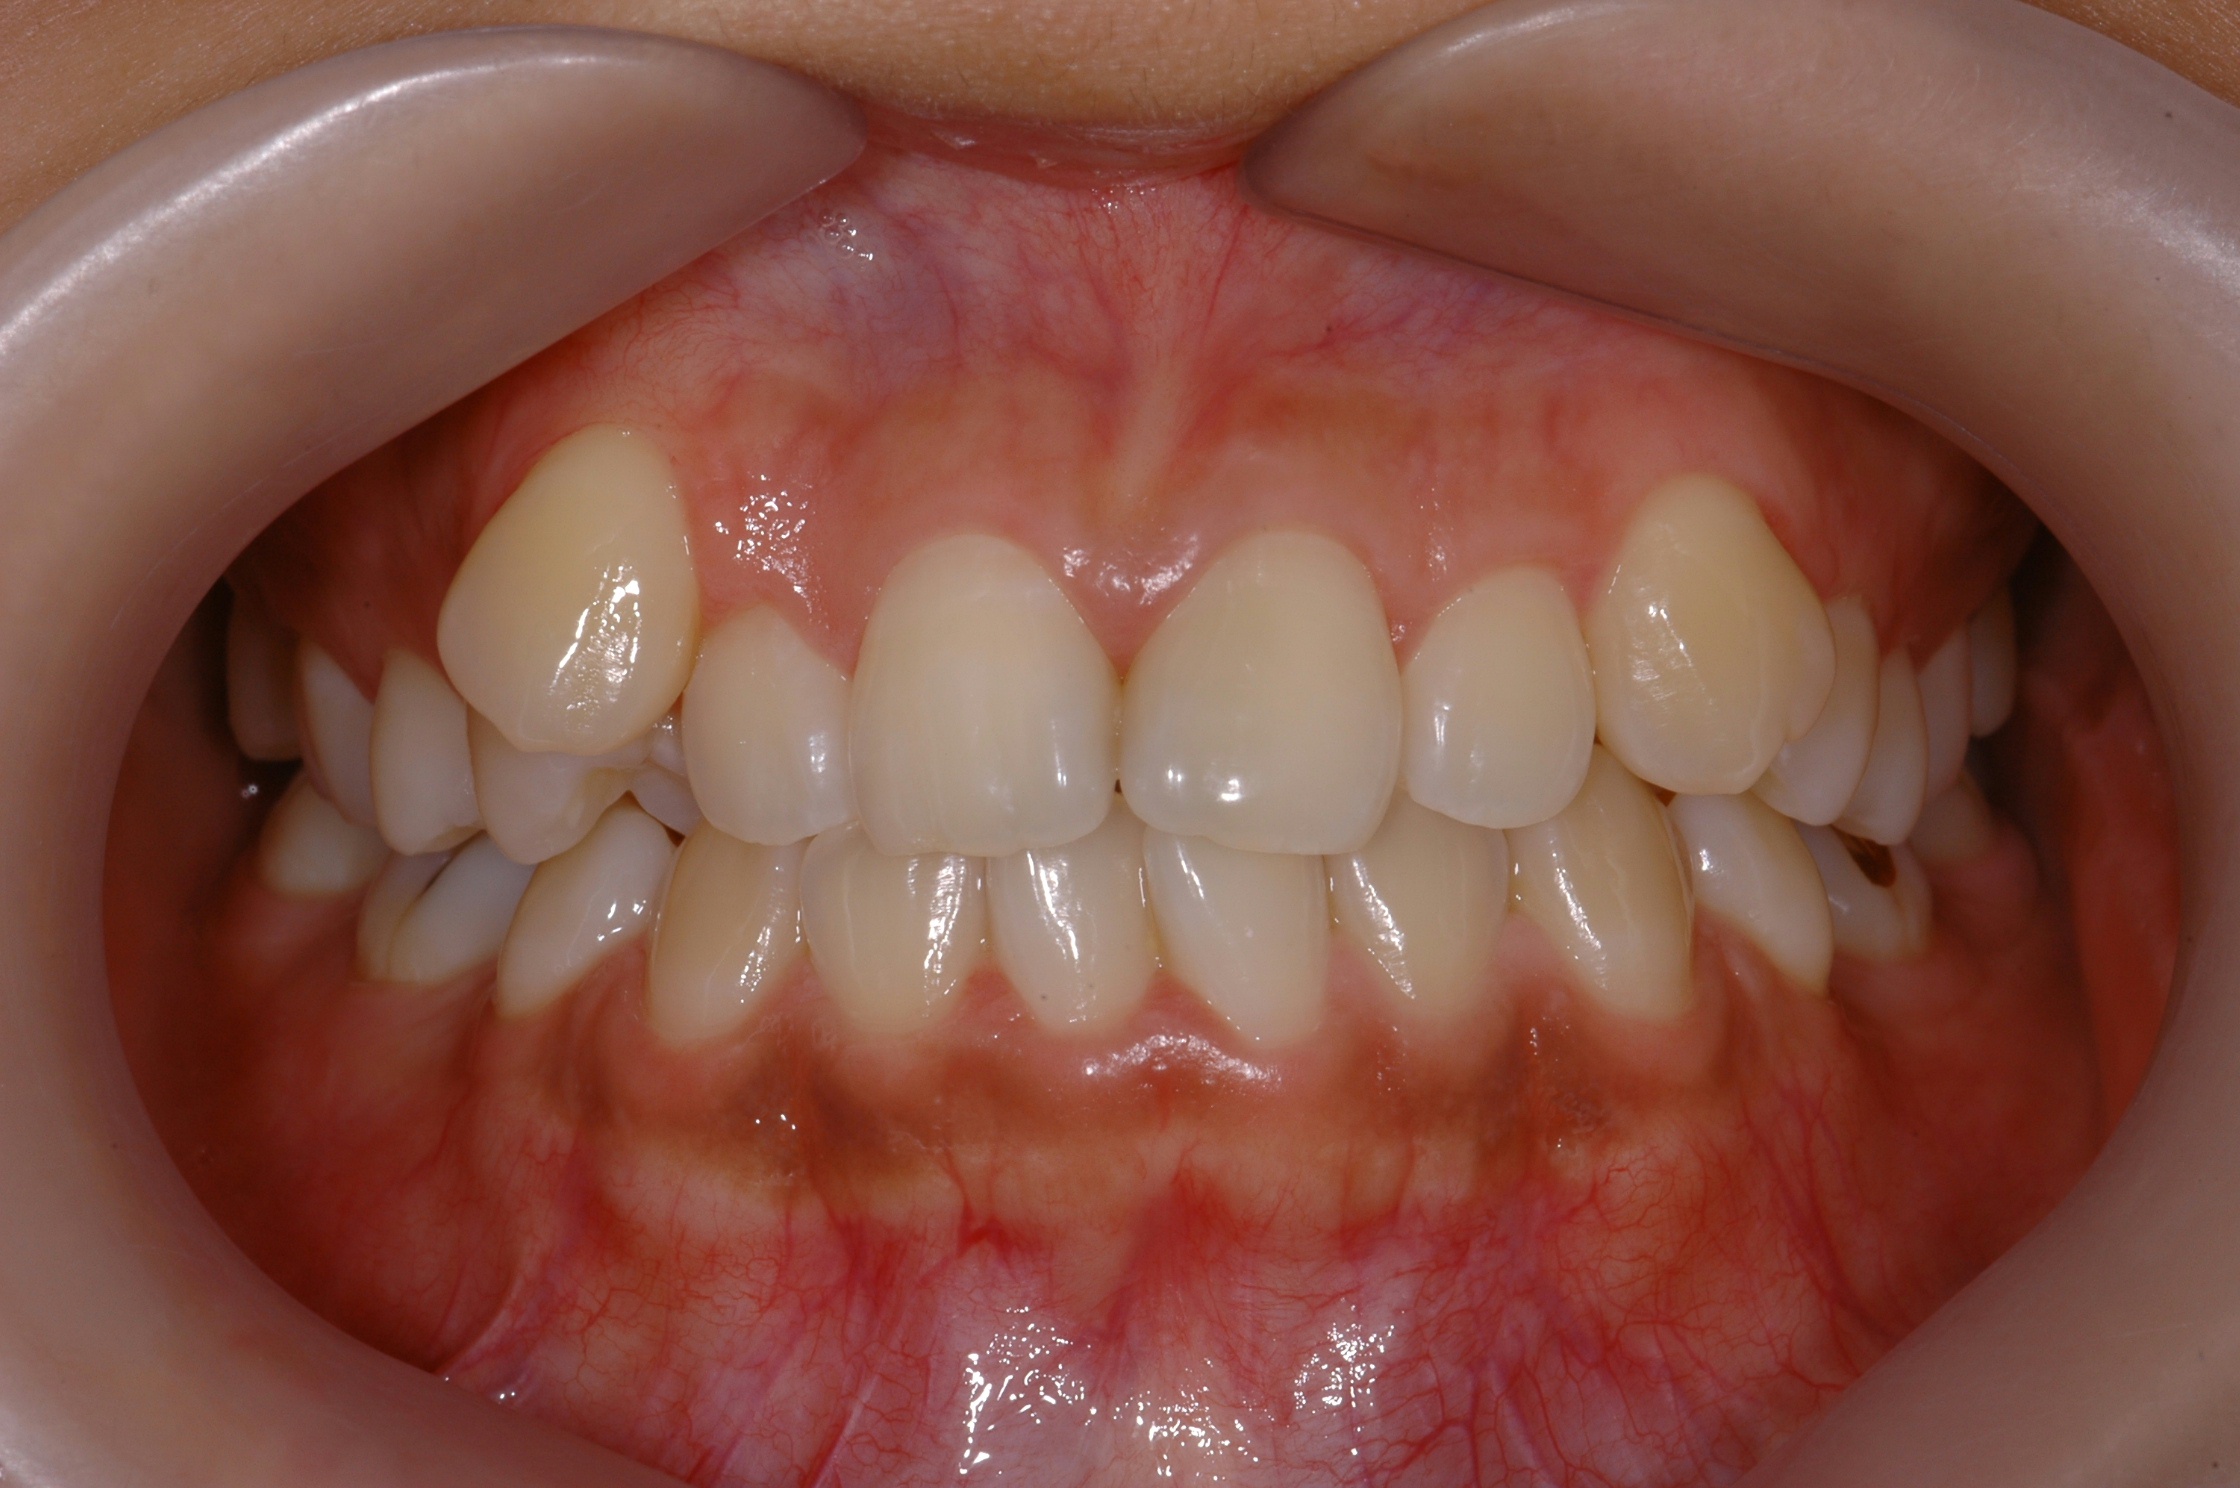

치료 전 사진입니다.